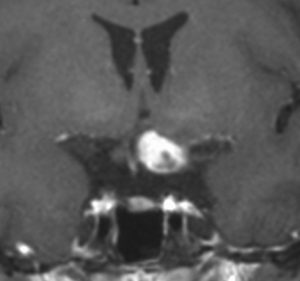

生後7カ月の幼児です。目が揺れるようになり(振り子様眼振)眼科を受診して腫瘍が発見されました。小児脳腫瘍の治療ができる病院へと紹介されました。

1ヶ月後にまたMRI検査がされました。乳児ですから検査にも麻酔が必要です。腫瘍は明らかに大きくなっています。左視神経から視索の腫瘍化が著しいので右側だけかすかに視力が残っているかもしれません。視力は明かりがわかる程度(明暗弁)と評価されました。

主治医の先生からこの赤ちゃんの両親に手術が提案されました。理由は,「とってみなければどんな腫瘍かわからない,病理診断ができないと制癌剤(化学療法)が選択できない」というものです。

こんなことを書くのは悪いことかもしれませんが,まったく馬鹿げた提案です。この画像はどこをどう見ても視路から発生した毛様粘液性星細胞腫です。画像はpathognomonic(日本語で火を見るよりも明らか)です。この小さな子に,全身麻酔をして開頭手術で生検病理診断すれば,それだけで3週間は化学療法の開始が遅れます。その間に明かりも見えなくなってしまう(完全失明する)可能性が高いでしょう。2021年時点でも,開頭手術による生検術は行われていますが,こんな重病の小さな子どもの頭を無用に開くなど,私にはもう理解不能です。